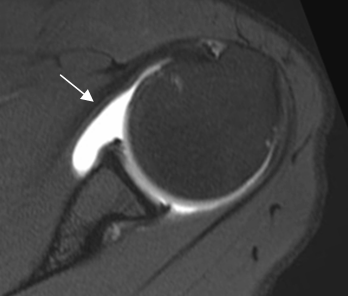

Fig 27. Labrum normal.

A, B, C y D: RM axial en FFE. Distintas configuraciones normales del labrum anterior.